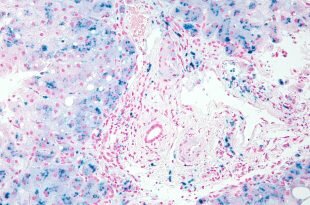

Важность печени заложена в ее функционале, благодаря которому поддерживается работоспособность других органов и систем, поэтому любые патологии железы чреваты серьезными нарушениями с ухудшением общего состояния человека. Помимо распространенных печеночных заболеваний (цирроз, дистрофия, рак), существуют недуги, встречающиеся с меньшей вероятностью, но оттого не менее опасные. Речь идет об энцефалопатии, когда повышается концентрация аммиака из-за потери печенью метаболической способности по отношению к белкам (состояние чревато путаницей сознания, комой), портальной гипертензии, провоцирующей развитие варикоза внутренних органов, увеличение селезенки (вплоть до инфаркта).